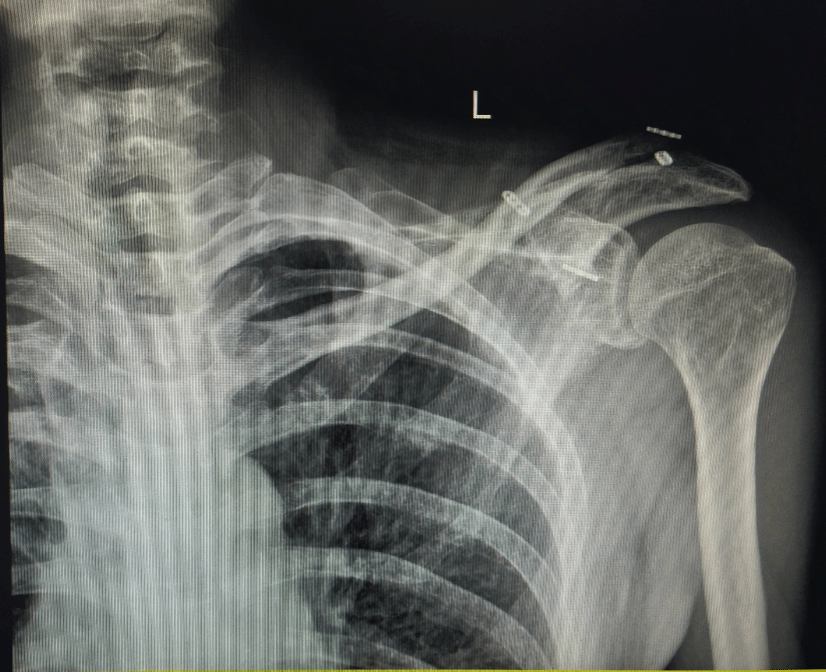

入院后,骨科中心关节与足踝病区张晨教授团队迅速展开术前评估,完善肩关节三维重建及MRI等检查。结果显示,患者左侧锁骨远端严重毁损,合并肩锁关节脱位。传统钢板复位难度较大,且术后功能恢复存在挑战,患者对二次手术取出钢板存在较大焦虑和抵触情绪。团队在积极完善术前准备的同时,重新评估并优化手术方案。经过慎重考量,团队决定采用创新的悬吊缝合桥技术,以期达到良好的治疗效果,同时避免患者因钢板取出而经历二次手术。经充分的术前讨论并取得患者及家属知情同意后,手术于2025年3月6日顺利实施。术中,骨折端对位良好,肩锁关节复位稳定,患者现已出院并在康复指导下开展功能训练。

术后复查X线片

与传统钩钢板技术相比,悬吊缝合桥技术具有诸多优势。首先,该技术在提供稳定固定的同时,无需取出内植物,患者可避免二次手术,极大降低术后痛苦。其次,弹性固定方式为术后早期活动提供足够空间,有助于患者尽早开展功能锻炼,提高术后恢复质量。此外,相较于钩钢板,患者术后异物感明显降低,舒适度更高。该创新技术的成功应用,为锁骨远端骨折合并肩锁关节脱位的治疗提供了一种更加微创、高效的选择,也标志着我院在骨科创新治疗领域取得了新的突破。